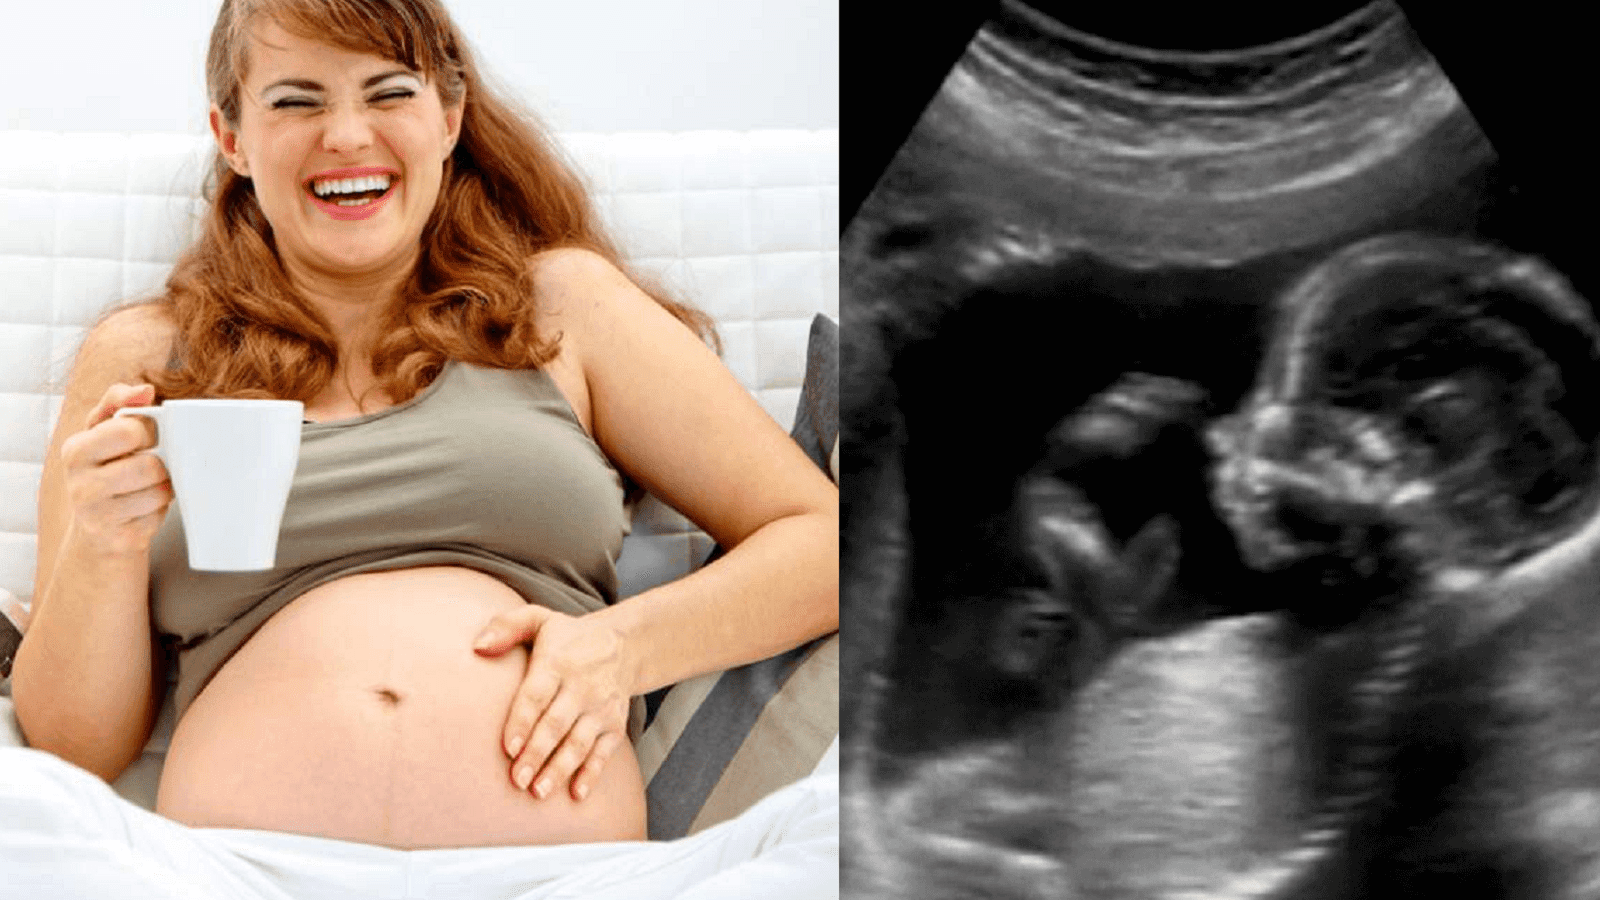

Σωματικά, το μωρό κινείται πάνω και κάτω όταν γελάει η μητέρα.

«Όταν παρακολουθούμε το έμβρυο στο υπερηχογράφημα και η μητέρα αρχίζει να γελάει, μπορούμε να δούμε το έμβρυο, να είναι ανάποδα στη μήτρα και το κεφάλι να πηγαίνει πάνω κάτω σαν να αναπηδά σε ένα τραμπολίνο» δήλωσε ο Janet DiPietro, από το τμήμα ερευνών του John Hopkins. «Όταν οι μητέρες παρακολουθήσουν στην οθόνη τι γίνεται στη μήτρα τους, γελούν πιο έντονα και το έμβρυο ανεβαίνει και κατεβαίνει ακόμα πιο γρήγορα. Αναρωτιόμαστε αν αυτός είναι ο λόγος για τον οποίο αρέσει στους ανθρωπους το τρενάκι του λούνα παρκ.»